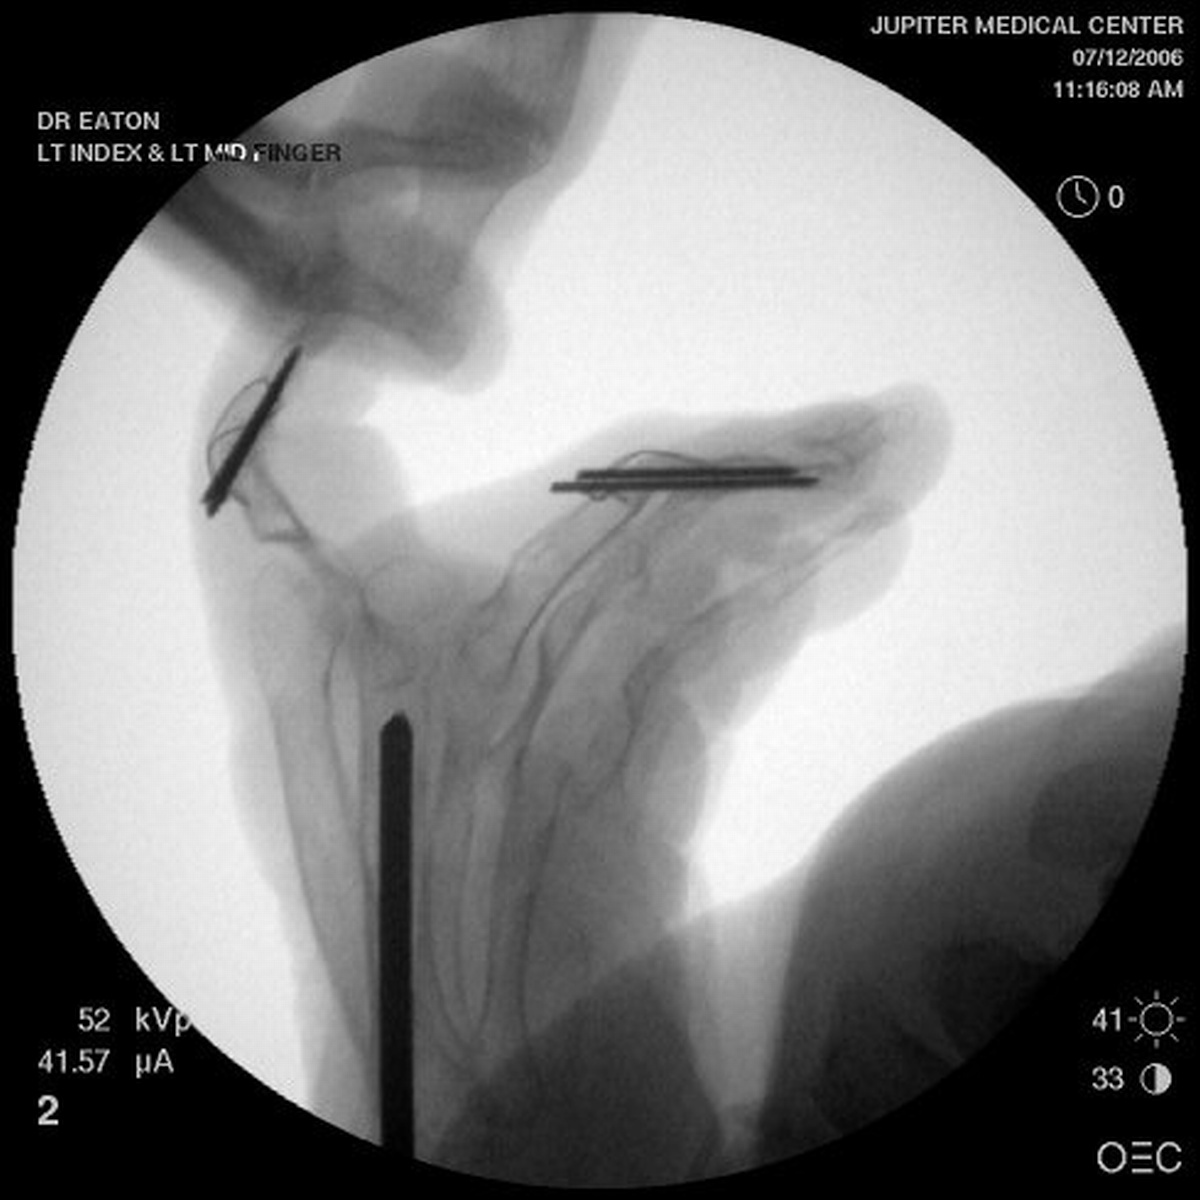

For the second stage of her reconstruction, the index proximal phalanx did not have adequate dorsal cortex to support an implant arthroplasty, and bone graft from the metacarpal head was used to reconstruct this.

The technique is shown in this video.

1. Initial exposure, pin removal.

2. Metacarpal head removed with saw.

3. Proximal phalanx stem path developed.

4. Jarvik suture passer for cerclage wires.

5. RCL ligament bone suture placed.

6. Bone graft tailored and secured.

7. Trial and final implant placed.

8. RCL repaired.

9. Capsular closure

10. Extensor repair.